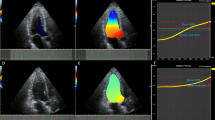

Pattern C

The streamline map shows that the blood flow within the whole LV chamber keeps a rotational motion during the IVR period. The flow in the posterior part of LV cavity is directed toward the apex and the flow in the anterior part is directed toward the base (Fig. 3, top row). A large vortex occupies all or most of the LV chamber and persists throughout the IVR period in the vortex map (Fig. 3, bottom row).

An IRF corresponding to pattern C in a 63-year-old male patient with dilated cardiomyopathy analyzed from apical long-axis view. The streamlines show that the blood flow within the LV chamber keeps a circulatory motion during the IVR period (top row). A large vortex occupies the LV chamber and persists throughout the IVR period (bottom row). AO aorta, LA: left atrium, LV: left ventricle.

The vast majority of patients with restrictive LV filling demonstrated IRF as pattern C. In these patients, a large vortex occupied almost all the LV chamber during the IVR period (Fig. 3). The global motion of blood flow in the basal-to-apical direction was diminished or disappeared.

Our previous studies have demonstrated that a large intraventricular vortex persists throughout the whole LV ejection phase and continues into the IVR period in patients with severely depressed LV function and enlarged LV chamber14,23. Likewise, in the present study, patients with pattern C had severe LV dilation and dysfunction. They showed significantly higher E/A ratio (>2) and E/e′ ratio (>15). The markedly depressed LV relaxation and elastic recoil severely reduced the ability of the ventricle to generate a diastolic intraventricular pressure gradient. LV diastolic suction performance during IVR was partly or entirely lost, the large vortex could not be dissipated, and it persisted throughout the IVR period. The appearance of the large sustained vortex during IVR should be a manifestation of severe LV diastolic dysfunction.